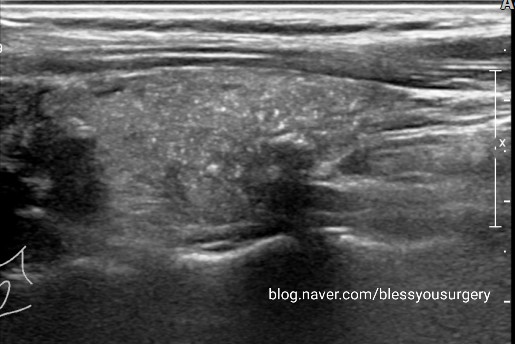

45세 여성의 건강검진상 우연히 발견된 오른쪽 갑상선 미세석회 초음파 사진입니다결절형이 아닌 우측 갑상선 전체에 퍼져 있는 백사립과 같은 미세한 미세석회화에서 세침검사를 실시하여 검사 결과 갑상선 유두상암 진단을 받았습니다.

진단은 초음파를 통하여 갑상선 결절의 크기 및 위치를 확인하고, 세침 검사를 통하여 작은 바늘로 혹에서 세포의 일부를 채취하여 진단합니다.갑상선 유두암의 경우 갑상선 호르몬의 수치는 거의 정상으로, 혈액 내 갑상선 글로불린이라는 물질은 전이된 갑상선 유두암에서 증가합니다.컴퓨터 단층 촬영, 방사성 요오드 스캔, 양전자 단층 촬영 등으로 전이 가부를 평가합니다.